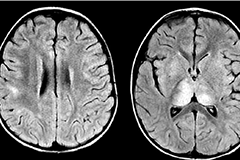

视神经脊髓炎和髓鞘少突胶质细胞糖蛋白

视神经脊髓炎(neuromyelitis optica, NMO)是指一种抗体介导的中枢神经系统(central ner...